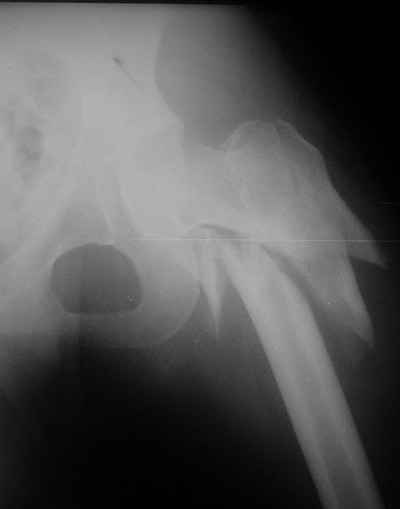

Мы закончили репозицию отломков бедренной кости в аппарате (рис. 1, 2) у нашей пациентки и на прошлой неделе сделали ей вторую операцию. Штифт удалось ввести закрыто. Верхний шеечный винт держался очень плохо, поэтому мы его убрали и решили не ставить. Нижний держал очень плотно. Рентгенограммы после операции прилагаю (рис. 3,4). Пока не получилось сделать нормальный аксиальный снимок (больная с трудом сгибает и отводит ногу в тазобедренном суставе). Пока сделали боковую проекцию в положении на здоровом боку со сгибанием здоровой ноги.